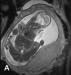

Abbildung 4: Pränatale Magnetresonanztomographie Fetus in der 32. SSW mit linksseitiger kongenitaler Zwerchfellhernie, koronale Schichtführung. Mit Hilfe der hier verwendeten Kontrastparameter können intrathorakal mit Mekonium gefüllten Darmanteile sehr hell dargestellt werden. Die Leber, sie ist etwas weniger hell als Mekonium, liegt intrabdominal. Am Hals ist auch die Glandula thyroidea zu erkennen. |

Abbildung 4: Pränatale Magnetresonanztomographie

Fetus in der 32. SSW mit linksseitiger kongenitaler Zwerchfellhernie, koronale Schichtführung. Mit Hilfe der hier verwendeten Kontrastparameter können intrathorakal mit Mekonium gefüllten Darmanteile sehr hell dargestellt werden. Die Leber, sie ist etwas weniger hell als Mekonium, liegt intrabdominal. Am Hals ist auch die Glandula thyroidea zu erkennen. |